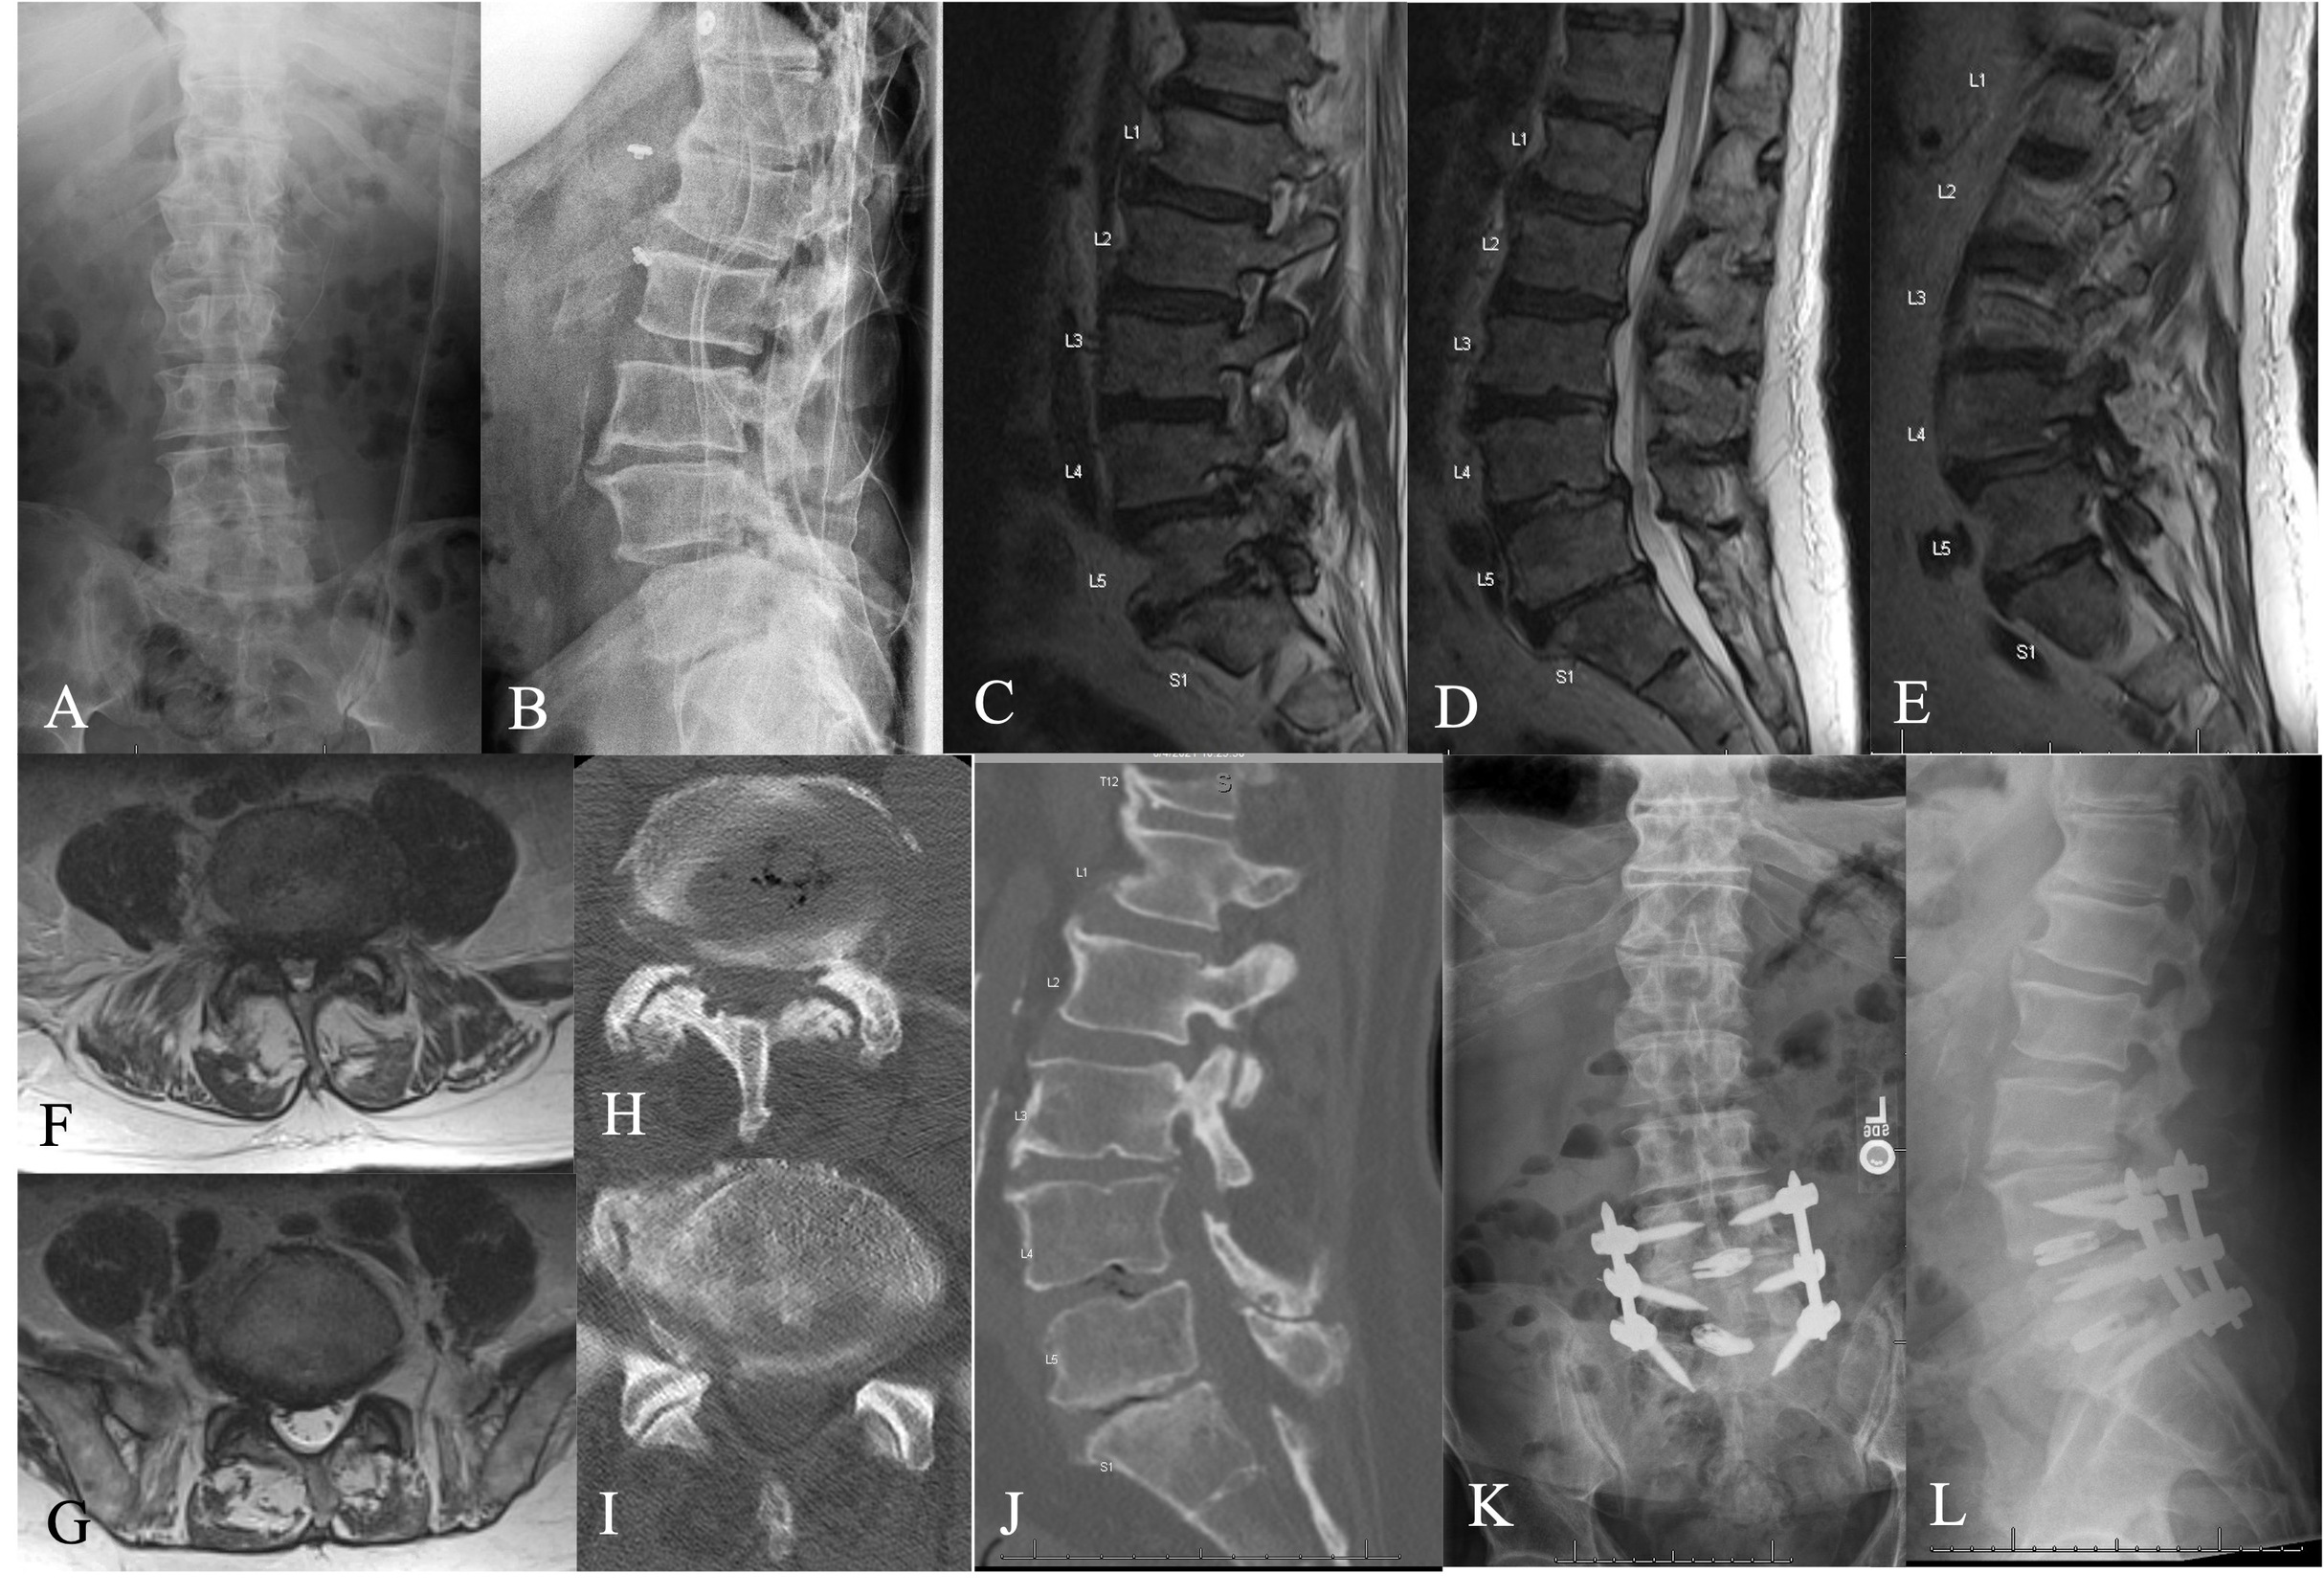

Lumbar spine plain radiographs revealed severe spondylotic changes in the form of disc height loss, osteophyte formation, and facet joint arthropathy at L4-5 and L5-S1 (Figure 2). The MRI of the lumbar spine revealed moderate-severe central and left lateral recess stenosis and severe left-sided foraminal stenosis in the setting of a posterior disc bulge, ligamentum flavum hypertrophy, and bilateral facet joint arthropathy. At L5-S1, severe right-sided foraminal stenosis was observed, largely in the setting of a posterior disc bulge and facet joint arthropathy. Following conservative management, we indicated him for a minimally invasive TLIF at L4-5 and L5-S1.